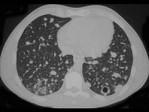

问题 男,32岁,咳嗽,咳脓痰伴发热、胸痛一月余,抗感染治疗不见好转,PPD(-),结合CT图像,最可能的诊断是 ( )

选项 A.肺炎 B.肺结核 C.肺脓肿 D.肺癌 E.肺放射菌病

答案 E